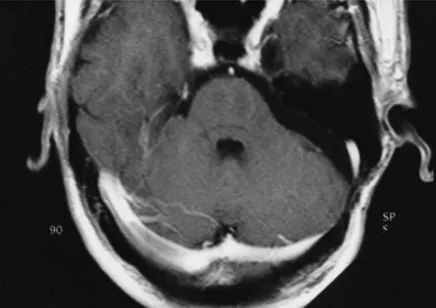

术后21个月轴位T1加权图像显示病灶完全切除,占位效应消失。

术后21个月轴位CISS图像显示无肿瘤残留或复发。